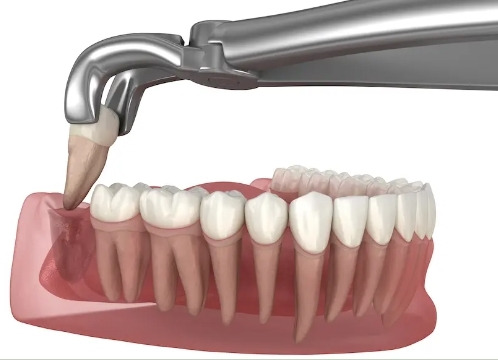

사랑니 발치 후 붓는 이유

사랑니는 일반 치아보다 큰 경우가 많습니다.

게다가 잇몸 깊숙한 곳에 있어요.

큰 치아가 깊숙한 곳에 단단히 박혀있으니,

이런 치아를 뽑아내려면

주변 조직에 자극이 가해질 수밖에 없죠.

그럼 우리 몸은 상처를 치유하기 위해

해당 부위로 혈액과 면역세포를 보냅니다.

그 과정에서 자연스럽게 붓는 거예요.